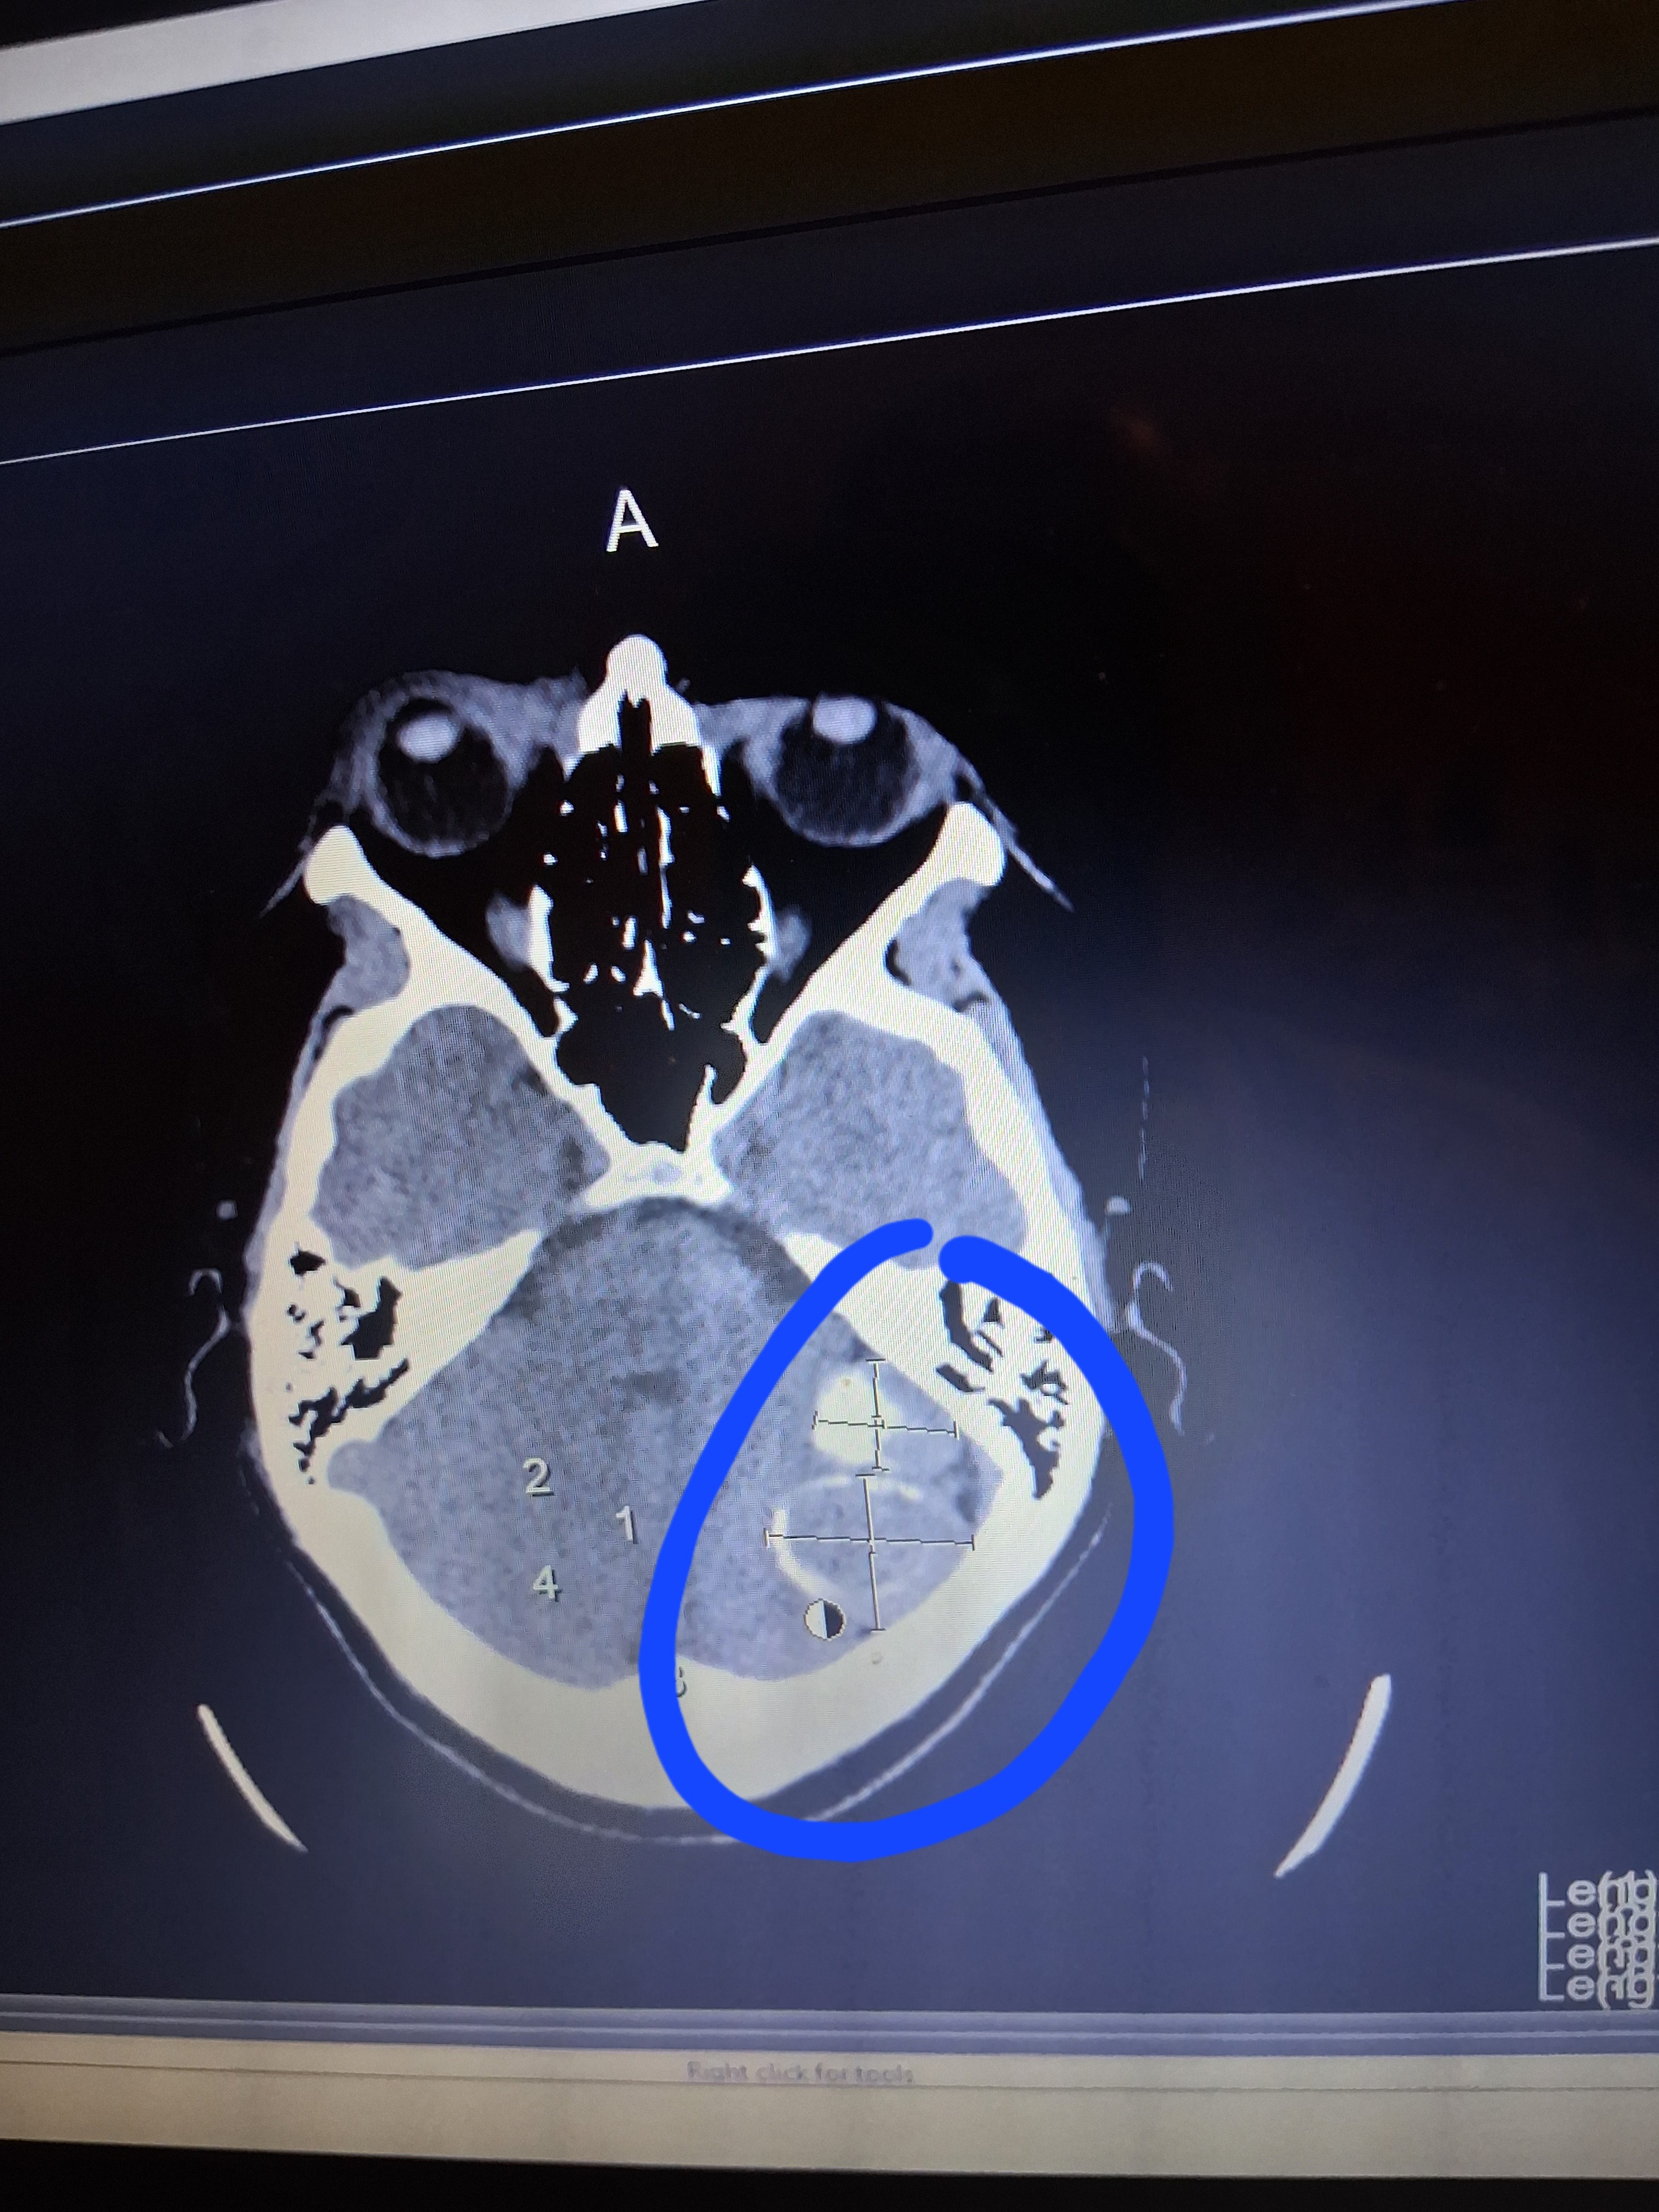

I have already 2 MRI's, and 2 C.T. scans, which showed 2 tumors, on the left side of my brain, and they are attached to one of the blood passages, on the left side of my head. I have 2 more scheduled MRI's, March 31st, and from there I will be scheduled to remove the MENINGIOMA.